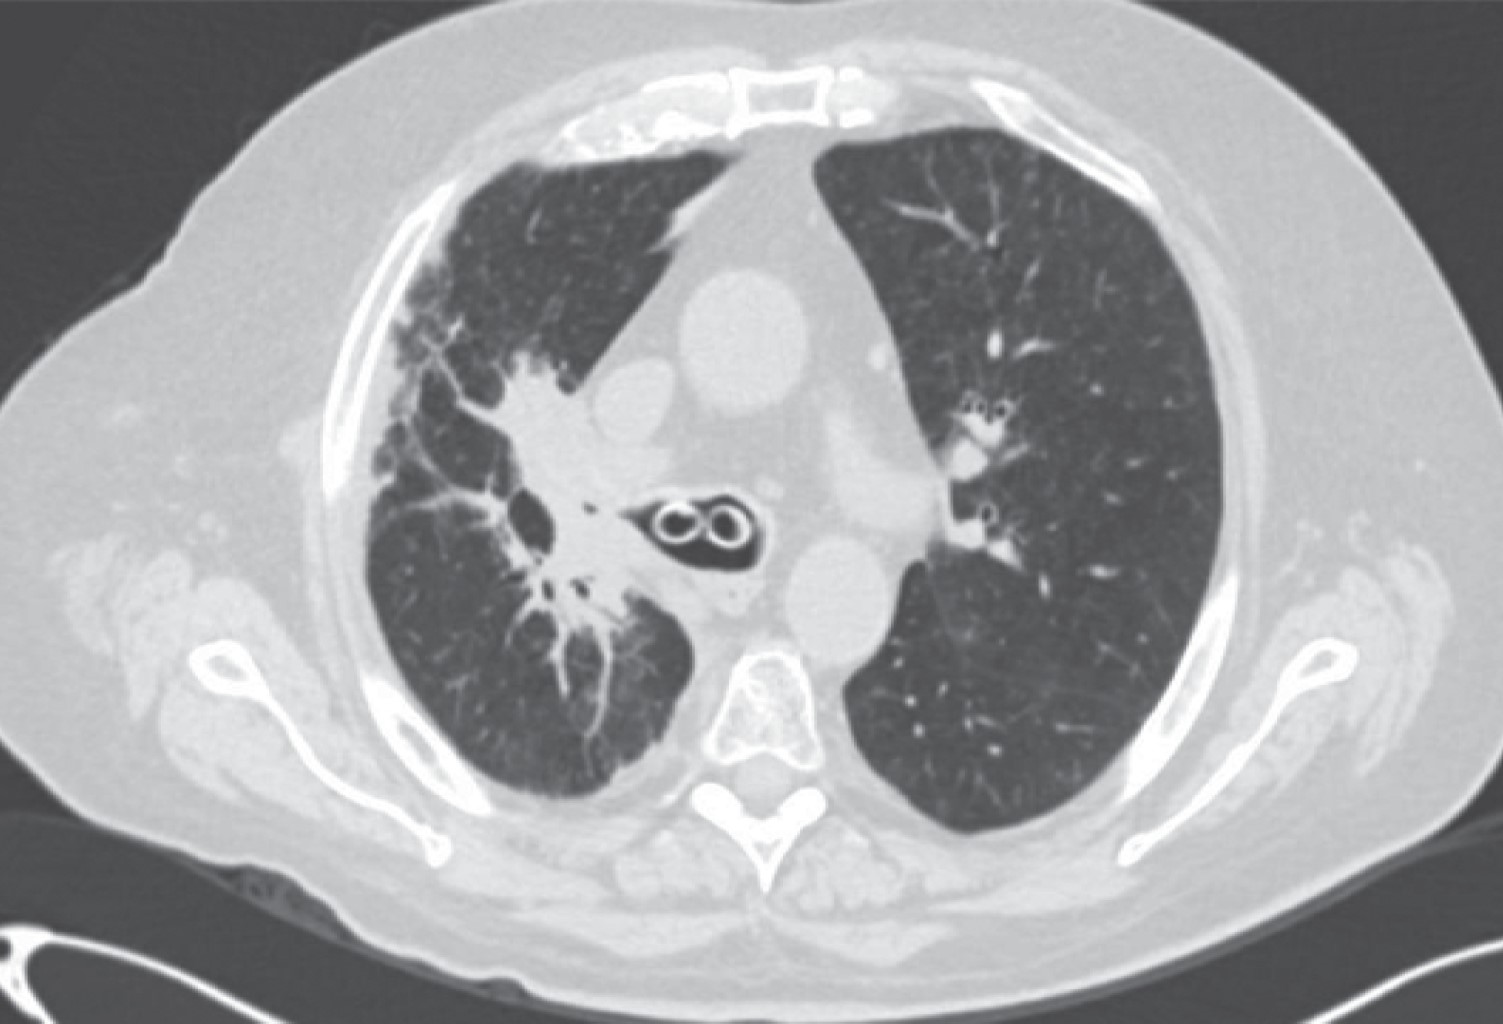

The appearance of a multiple primary malignant neoplasms is more frequent in elderly patients, lung cancer is the leading cause of cancer death worldwide, the frequency of synchronous and metachronous lung cancers has increased in recent years due to advances in early detection techniques, multiple malignancies can be classified as synchronous or metachronous according to the time of onset in relation to the first malignancie, synchronous those that appear in the first six months and metachronous as those that appear after six months. We present the case of a 66-year-old male patient with a history of right radical nephrectomy for clear cell renal cancer, who goes to the emergency department seven years later for respiratory symptoms and hemoptysis. In his study protocol, he is diagnosed with a parahiliary right upper lobe endobronchial tumor of epidermoid lineage involving the right bronchus.

Figure 2